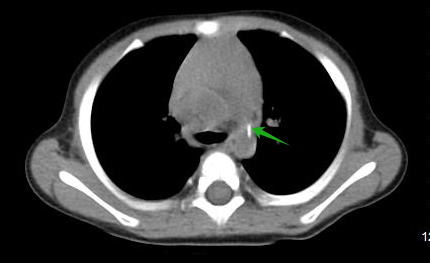

案例四

小杨,1岁3月,进食花生时出现呛咳,因“咳嗽喘息5天,加重2天”收住院。入院查体左侧呼吸音减低伴喘鸣,完善胸部CT检查,发现左主支气管管腔内大小约 5.8mm×5.6mm×6.8mm不规则密度影,左肺透亮度增高,考虑左主支气管异物伴左侧阻塞性肺气肿,行“气管镜气管异物取出术”,取出半颗花生。

(箭头为左主支气管异物)